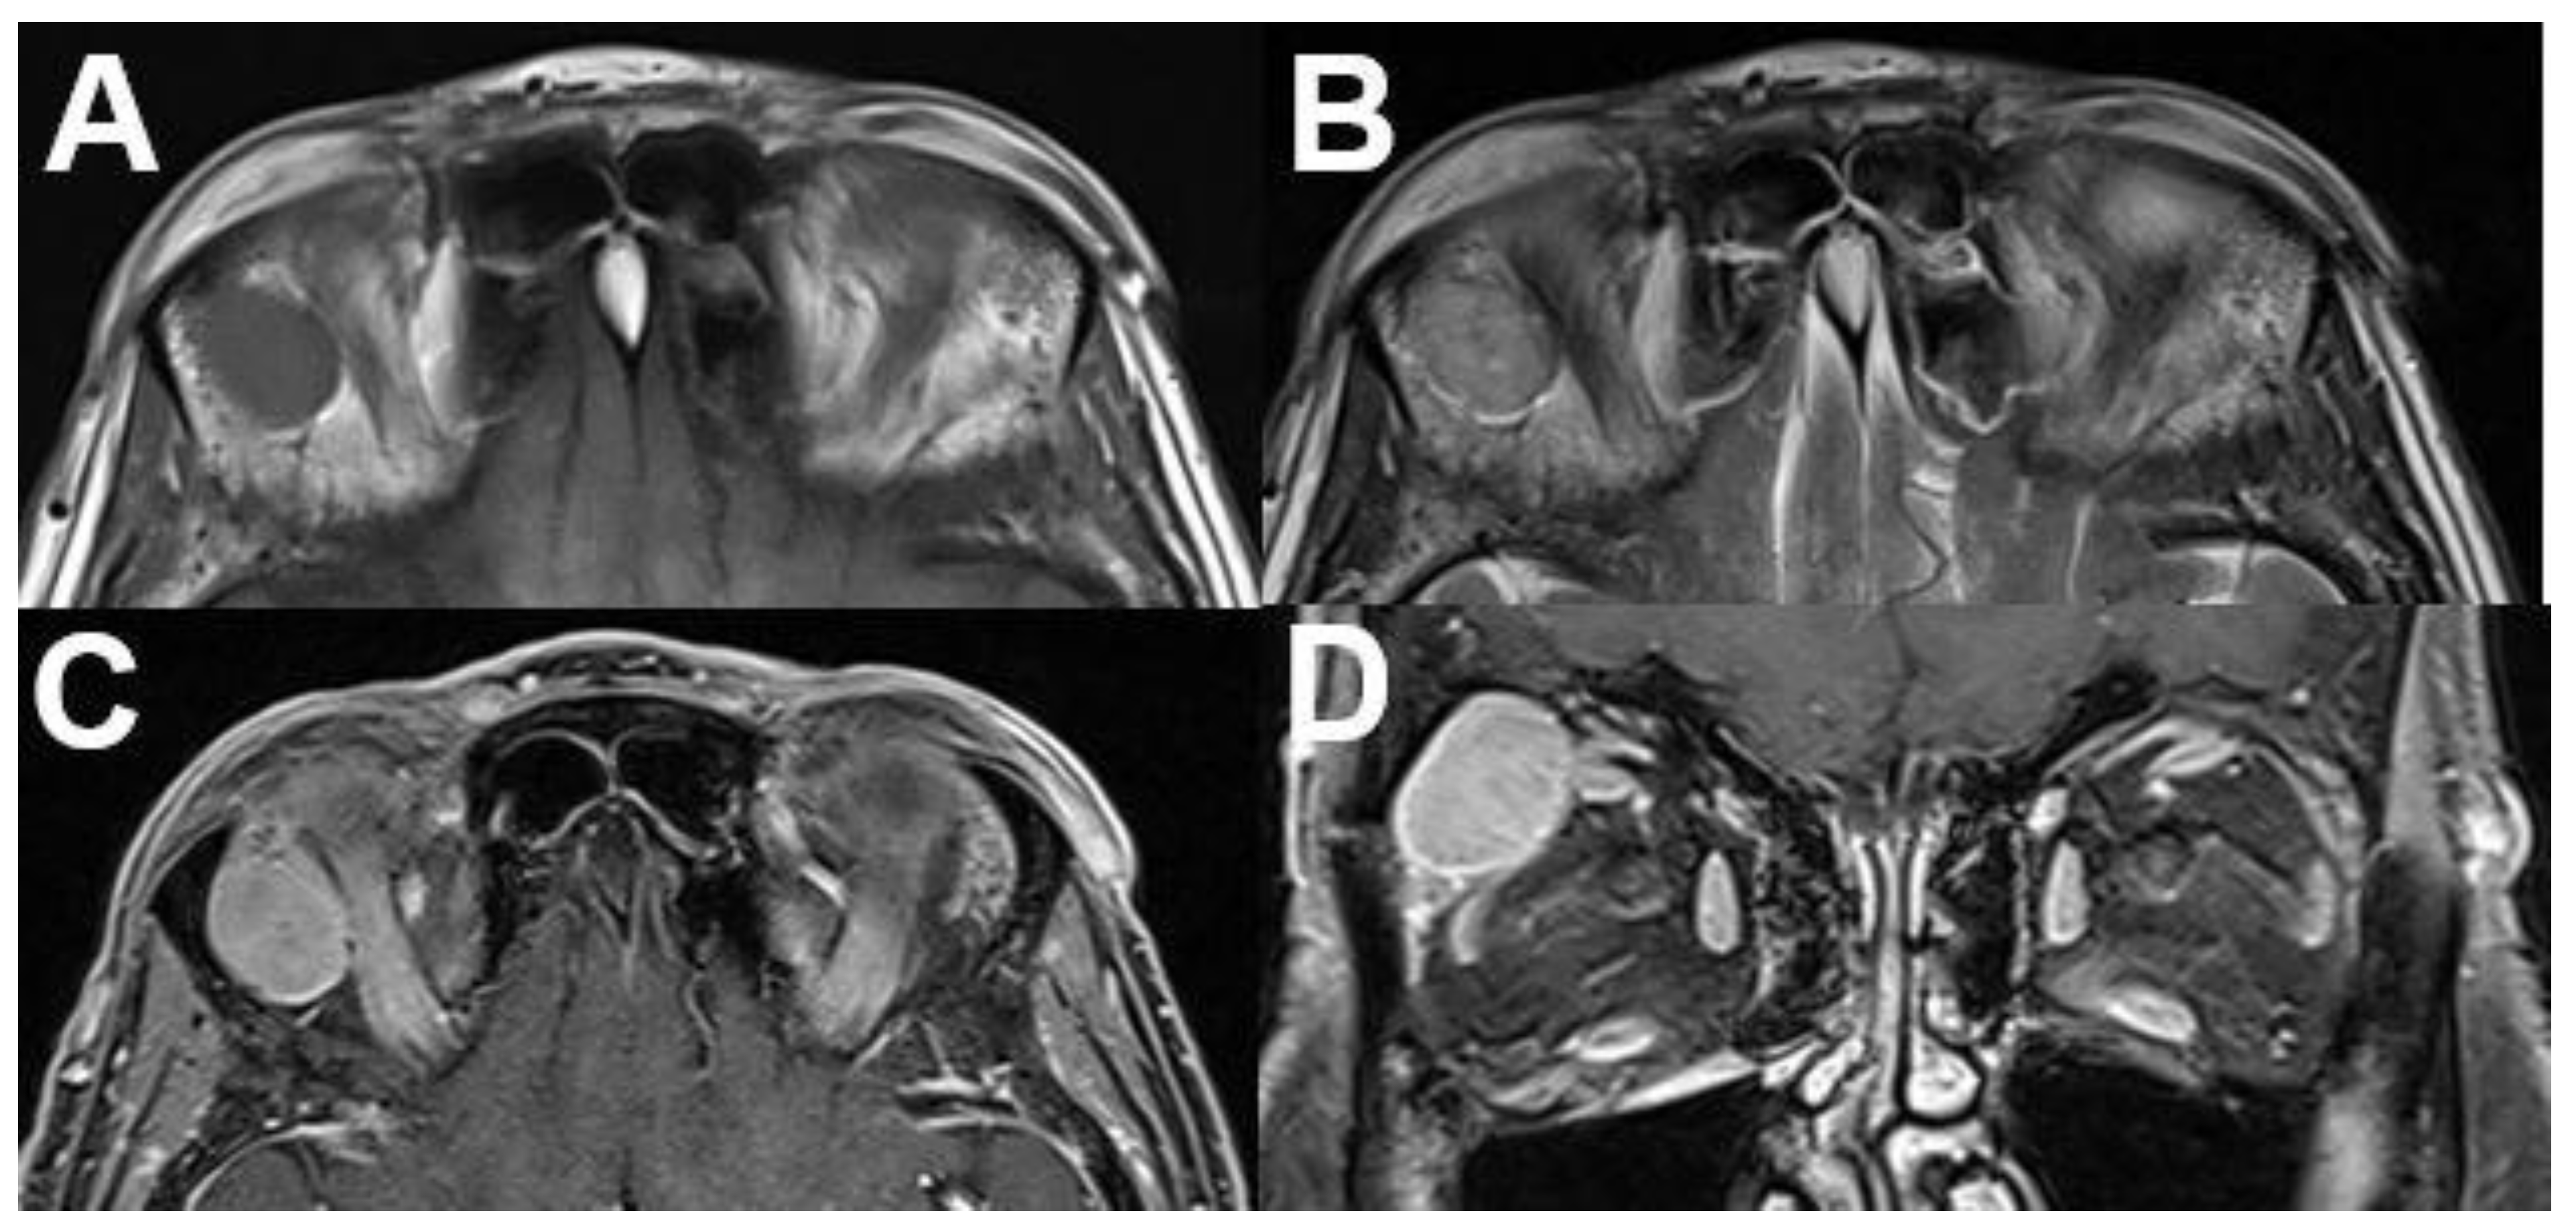

3.6. Masses with Involvement of Different Parts of the Orbit

3.6.1. Metastasis

3.6.2. Rhabdomyosarcoma